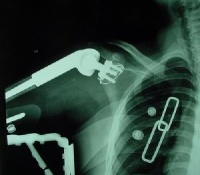

(1)骨盆后前位X线片:X线平片检查一般可明确骨折部位骨折类型及其移位情况,亦常能提示可能发生鵻的并发症。全骨盆后前位X线片可显示骨盆全貌对疑有骨盆骨折者应常规拍摄全骨盆后前位X线片以防漏诊对骨盆后前位X线片上显示有骨盆环骨折者,为明确了解骨折移位情况还应再摄骨盆入口位和出口位片。(2)骨盆入口位片:患者仰卧,X射线从颅侧投向尾侧,与片盒成60°倾斜摄片本位片可显示耻骨段骨折移位;骨盆向内、向外旋转和向内移位的程度;骶髂关节向后移位及骶骨骨折是否侵犯椎管;同样可显示坐骨棘撕脱骨折。

(3)骨盆出口位片:X线是从尾侧投向颅侧,与片盒成45°角本片可显示桶柄型损伤与耻骨体骨折,对确定半骨盆有无向上旋转移位是很有用的,在本片上同样可显示骶骨或髂骨骨折移位情况。

CT检查对骨盆骨折虽不属常规但它可在多个平面上清晰显示骶髂关节及其周围骨折或髋臼骨折的移位情况,因此凡涉及后环和髋臼的骨折应行CT检查骨盆三维重建CT或螺旋CT检查更能从整体显示骨盆损伤后的全貌,对指导骨折治疗颇有助益但应铭记对血流动力学鵻不稳定和多发伤患者,后前位全骨盆X线片是最基本和最重要鵻的放射学检查不要在拍摄特殊X线片上花费时间,更为重要的是尽快复苏。